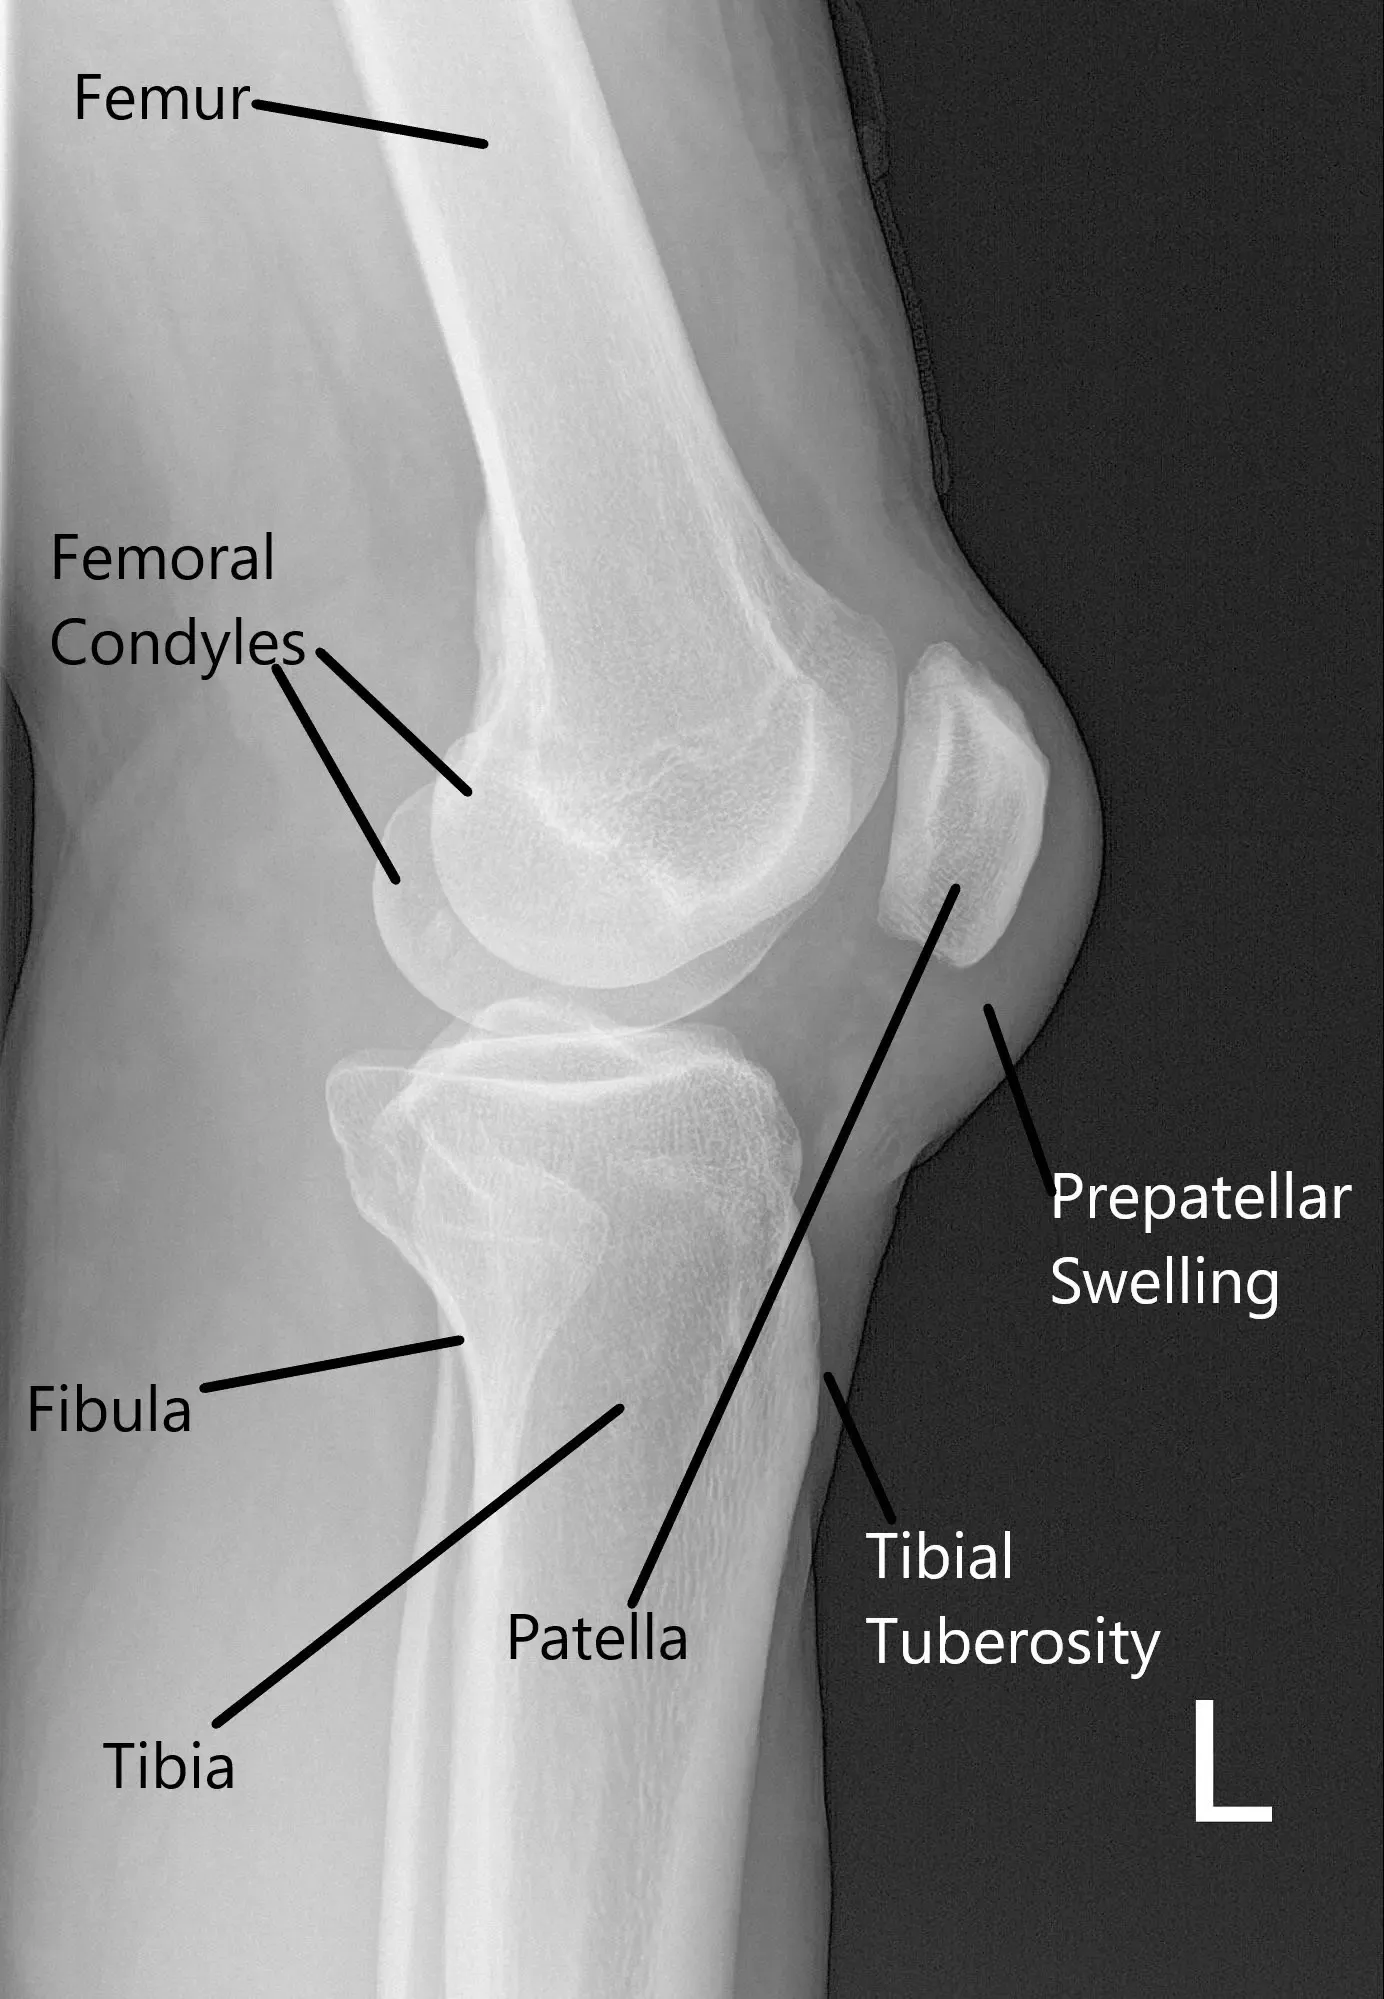

X-ray of the left knee suggested a soft tissue swelling anterior to the patella and patellar tilt.

X-ray of the left knee in lateral view.